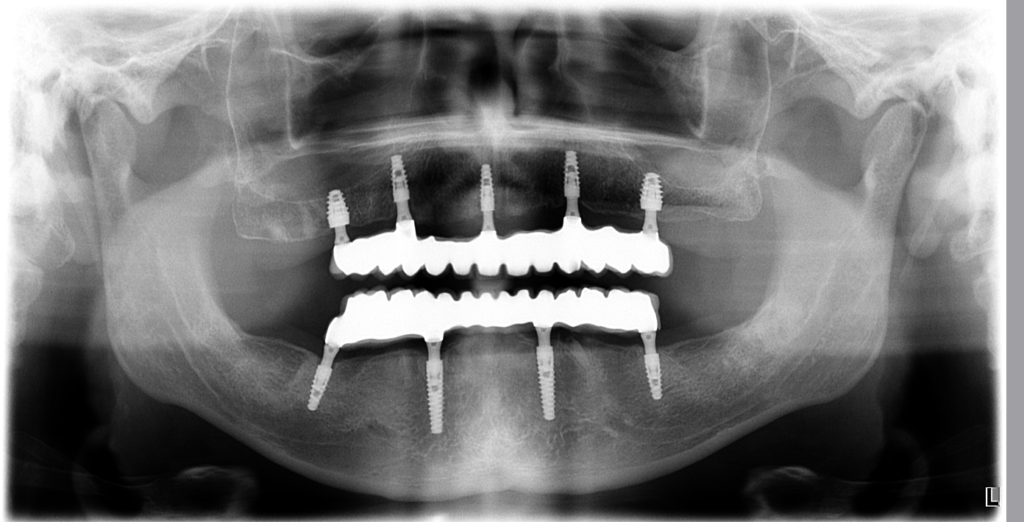

Fotografia po troch rokoch ukazuje, že výsledok je stále rovnako krásny, ako v deň dokončenia.

RTG snímka zas potvrdzuje stabilitu implantátov a zdravé okolité tkanivá.